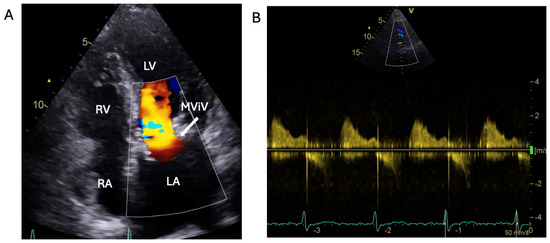

1.1.3. Case 3

2.3. The Saga of Relapsing IE of the Prosthetic Mitral Valve Causing Structural Valve Degeneration and Transcutaneous MViV Prosthesis